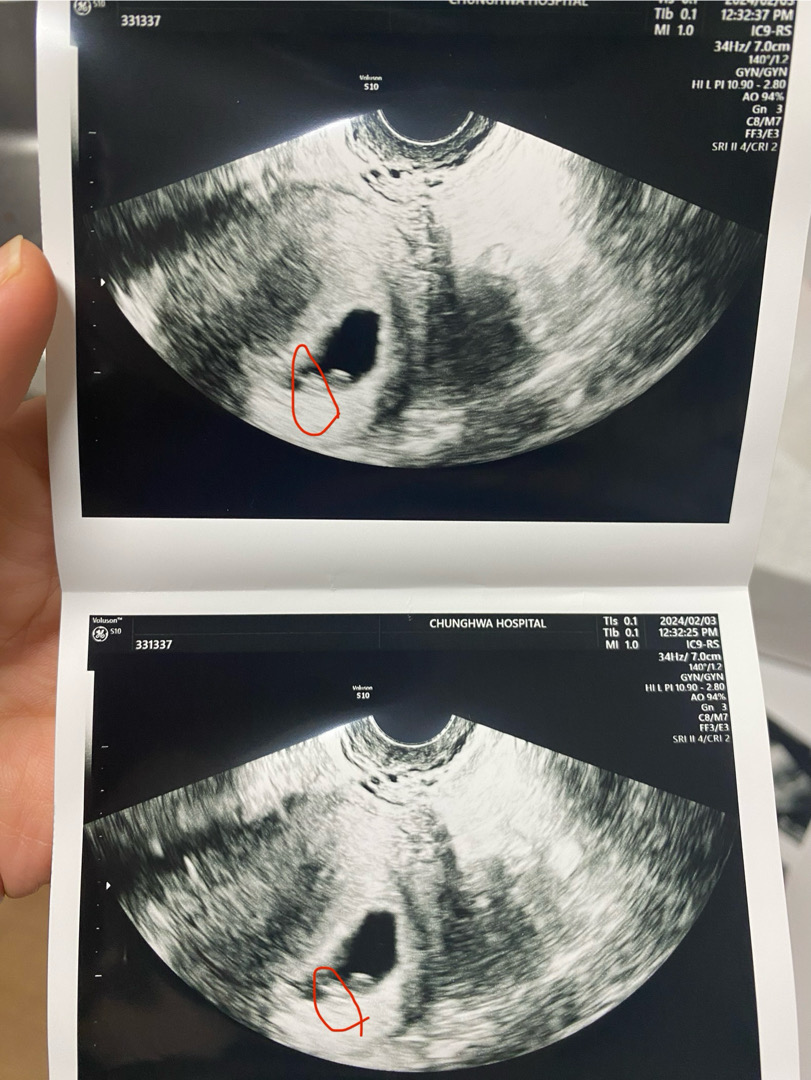

아기가 아기집 구석에 붙어있다고 하는데 괜찮을까요?

우선 오늘 갔을 땐 6주4일 정도 인 것 같다고 하구 심소들으러 갔는데 심장소리도 100넘어서 정상이라고 하셨는데 애기가 구석에 붙어있네요 라고 하시더라구요.. 혹시 애기가 아기집 구석에 붙어 있었던 분들 계실까요? 그리고 이 때쯤 애기 크기가 다들 어떻게 되셨을까요?🥹